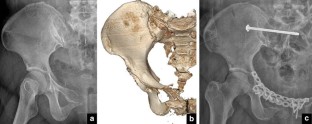

Fig. 3